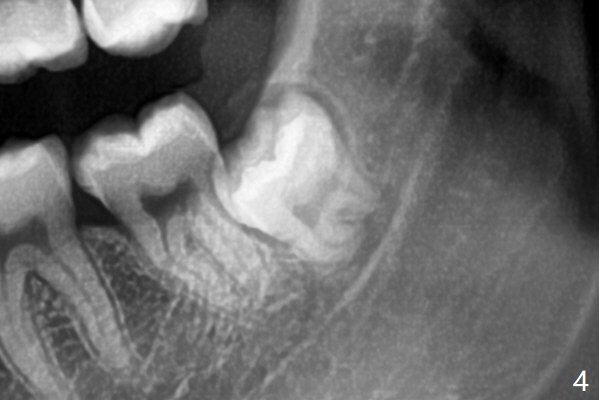

Since the third molars may overlap with the second ones, oblique incision (red line in Fig.4') will be mesial. Place Collagen and Osteogen plugs in the #32 and 17 sockets, respectively (Fig.4': C, O). As the roots are short and bone formation distal to the 2nd molars is critical, the plugs will be placed horizontally and coronally (Fig.4' white outline). No dovetail is needed.